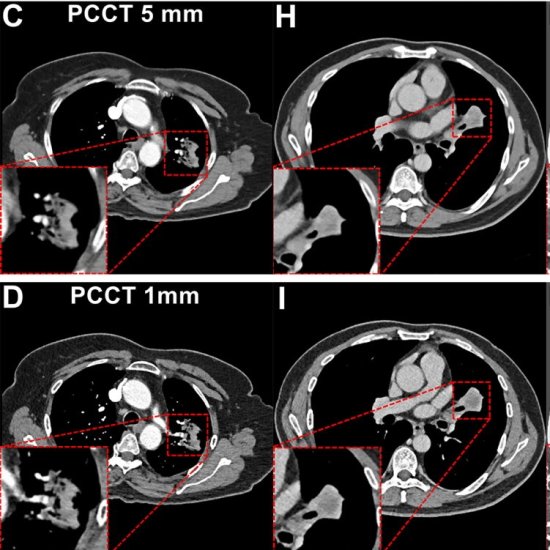

News • Sharper images, less radiation

A study of 200 lung cancer patients shows photon-counting CT cuts radiation by 66% and contrast agent by 27% - while delivering sharper images and better tumor detection than conventional CT. |